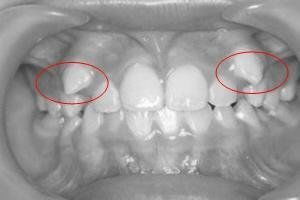

一般多生牙的產(chǎn)生的危害就是若長(zhǎng)在牙列里,就會(huì)占據(jù)正常牙的位置,由于正常牙受到多生牙的排擠,只好從牙齦的旁邊長(zhǎng)出去,導(dǎo)致牙齒排列紊亂。若多生牙長(zhǎng)在牙列的外邊,就會(huì)形成雙層牙,兩牙之間有縫隙,造成食物殘?jiān)鼫艉颓度?,?dǎo)致牙齦組織發(fā)炎,甚至還會(huì)引起齲齒的發(fā)生。這樣最好是及時(shí)進(jìn)行拔掉。

多生牙本來(lái)就是不應(yīng)該有的牙齒,而且還可能造成不良的后果。所以一旦發(fā)多生牙,就應(yīng)該及時(shí)請(qǐng)醫(yī)生鑒別并拔除。但是,仍有少數(shù)兒童在多生牙的生長(zhǎng)早期未被引起注意,而發(fā)現(xiàn)后長(zhǎng)在牙列中排列還算整齊,又不影響其他牙齒,咬合關(guān)系也未出現(xiàn)異常情況時(shí),可以考慮保留這個(gè)多生牙。